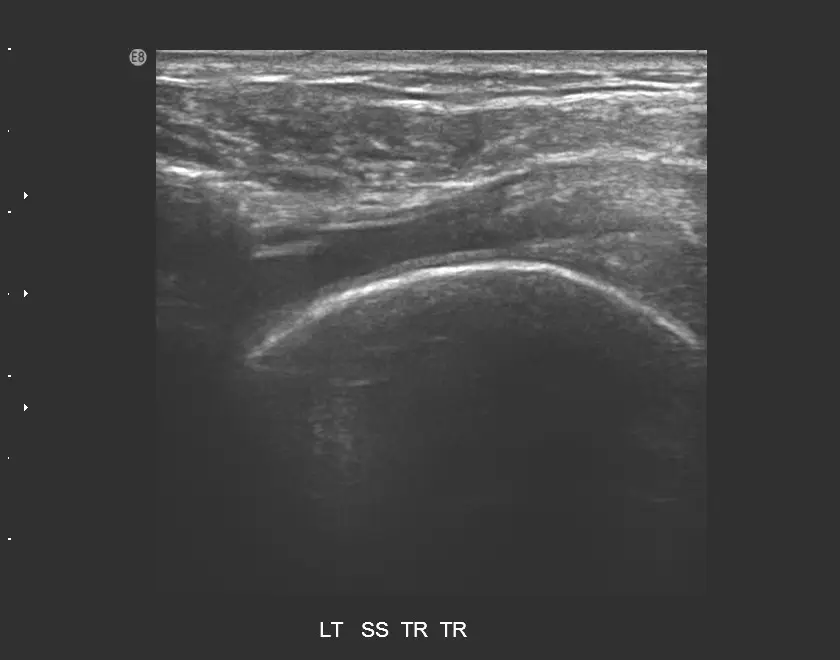

85 歲女性患者,主訴左肩疼痛超過 6個月,有局部壓痛,無肌肉萎縮現象,圖為左肩部超音波檢查,上圖為旋轉環帶長軸切面,下圖為短軸切面,最可能之診斷為何?

下圖(短軸切面,LT SS TR): 左肩棘上肌腱橫斷面(短軸)超音波影像。正常短軸切面下棘上肌腱應呈現橢圓形高回音結構,包含多點狀高回音纖維。本圖可見:

- 棘上肌腱正常橢圓形高回音結構消失